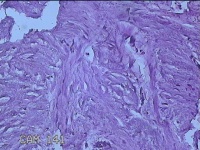

右膝前瘢痕增生组织

性别

女

年龄

38岁

临床诊断

右膝前瘢痕增生

一般病史

右膝前外伤后瘢痕增生4年余。

标本名称

大体所见

灰白粉红色组织6.5x5x1.8cm一块,表面光滑,切面灰白粉红色,质软。